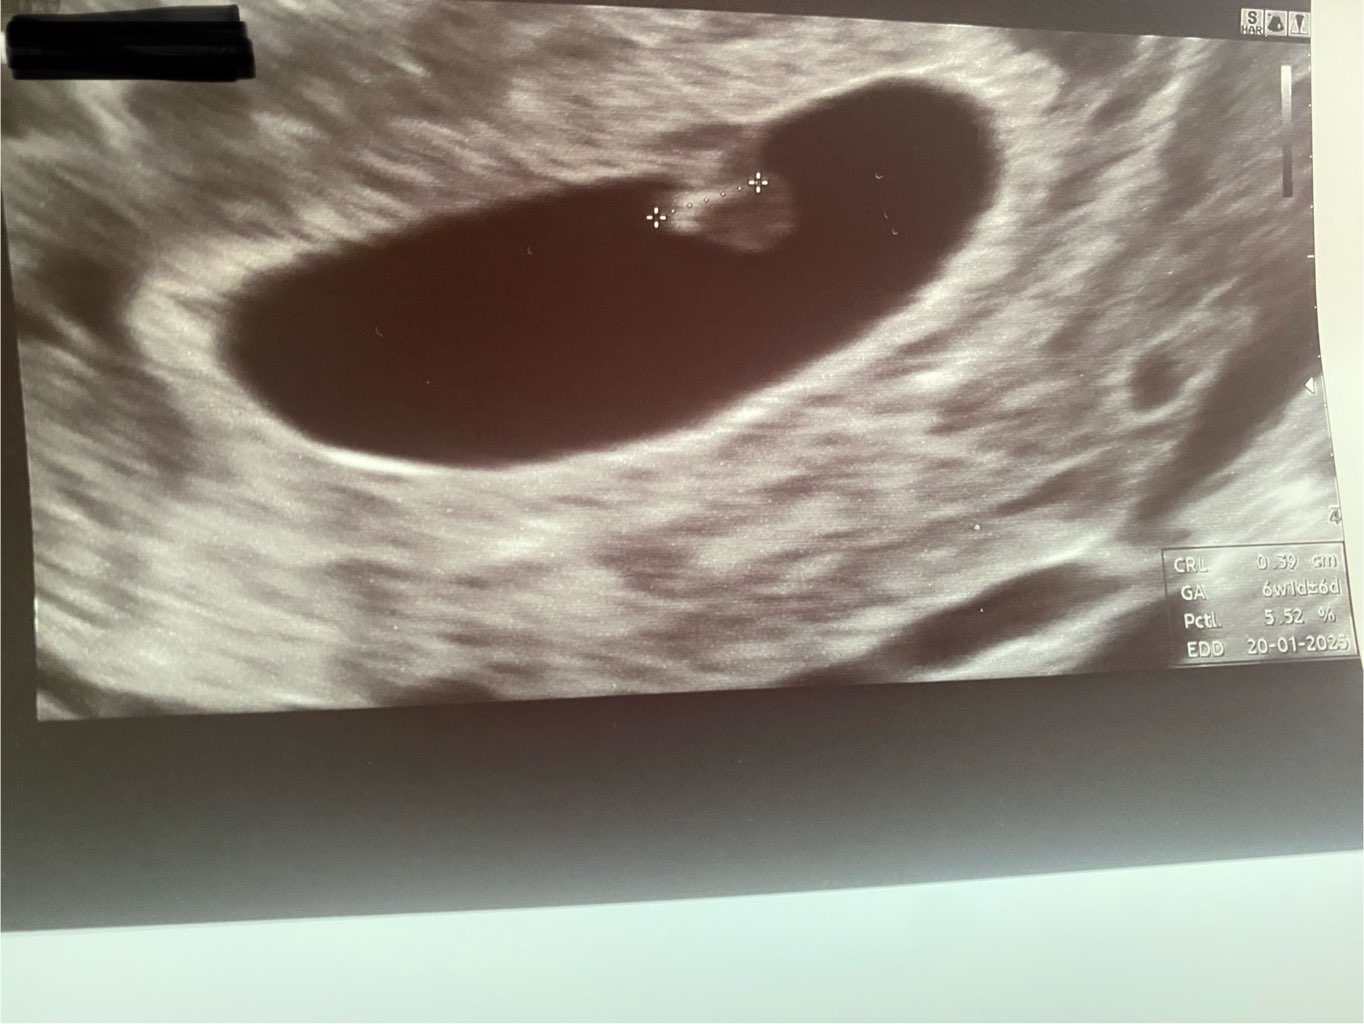

20ego września wyszedł mi pozytywny test oraz beta z krwi. Byłam na badaniu usg ginekologicznym 7ego października, gdzie lekarz powiedział, że albo ciąża rozwija się nieprawidłowo albo jest mlodsza (pęcherzyk 0,61cm). Określił ciążę na poniżej 6 tygodnia.

Dla własnego spokoju poszłam spontanicznie do innego ginekologa w ten poniedziałek 14ego. On znalazł pęcherzyk(10,8mm) i według badania usg wskazuję na 4w1d. Dodaje zdjęcie bo mam wrażenie,że te dwa pęcherzyki są w innych miejscach. Chyba,że to zależy od ustawienia głowicy? Napiszcie proszę co o tym sądzicie, czy lekarz mógł przeoczyć jeden pęcherzyk?

Dolne zdjęcie - 1 wizyta , u góry druga i porównanie obok siebie.